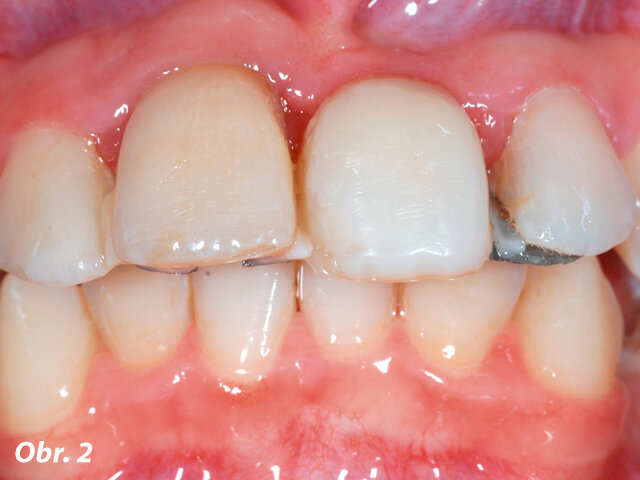

V 10 letech pacientka utrpěla trauma frontálních zubů s avulzí a replantací centrálních řezáků (zuby 11 a 21, dle značení FDI). Navzdory všem snahám nebylo možné zachovat zub 21. Předchozí zubní lékař tento zub nahradil metalokeramickým adhezivním můstkem (Marylandský můstek) (obr. 1 a 2). Naneštěstí byla v průběhu terapie potvrzena infaustní prognóza u zubu 11 – ten musel být extrahován během ortodontické léčby. Za účelem nahrazení obou centrálních řezáků byl zhotoven provizorní můstek s umělou gingivou, který byl připevněn na fixní ortodontické aparáty (obr. 3).

Obr. 2: Po sejmutí a refixaci vykazoval adhezivní můstek kompromisní dosed